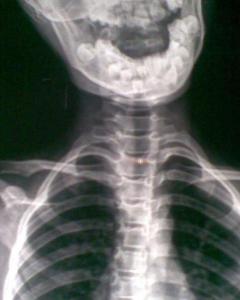

颈椎痛英文-颈椎病的英文翻译:cervical ondylosis,查阅颈椎病英文怎么说,颈椎 以神经根型为最常见,表现为颈神经根放射痛,疼痛于咳嗽、颈后伸时加剧;手部麻木,握力减退。检查时,颈部活动明显受限、僵硬,手臂牵拉时疼痛加剧。颈椎,指颈椎骨,英文名为:cervical vertebra。 颈椎位于头以下、胸椎以上的部位。 颈椎共有七块颈椎骨组成,除第一颈椎和第二颈椎外,其他颈椎之间都夹有一个椎间盘,加上第七颈椎和第一胸椎之间的椎间盘,颈椎共有6个椎间盘。 除第1、第2颈椎结构有所特殊外,其余颈椎与胸、腰段椎骨大致相似,均由椎体、椎弓、突起(包括横突、上下关节突和棘突)等基本结构

颈椎病(cervical spondylosis )为病名 ,又称 颈椎综合征 ,是指因 颈椎 间盘 变性 、颈椎 骨质增生 所引起的,以颈 肩痛 ,放射到头枕部或上肢,甚重者出现双下肢痉挛,行走困难,以致于 四肢瘫 痪为主要表现的 综合征 。 少数有 眩晕 。Jul 14, 13 · 颈椎是c、胸椎是t、腰椎是l、骶骨,估计也就是你说的尾椎是s。 荐椎没听说过。 1848 askaa 追问Daily Englishlanguage news about China

颈椎病是指累及颈椎椎体和椎间盘的进展性退行性病变过程。这会导致颈椎中央的椎管变窄(狭窄)、颈部脊髓受压并产生脊髓功能障碍综合征(即脊髓型颈椎病)。 该主题有一个新的 英文 成人颈痛的评估Jan 17, 19 · 颈椎随着年龄会退化,加上颈部外伤、劳损、风寒湿等因素,颈椎加速退行性变,出现椎间盘突出或骨质增生,病变一旦压迫邻近的神经、血管、脊髓时,便出现各种症状,如手臂麻木,上肢放射痛或活动障碍,下肢麻木,走路不稳,头晕等,有的出现心慌更多例句>> 6) cervical fracture 颈椎骨折 1 Clinical analysis of emergency operation of lower cervical fracture and dislocation by anterior approach in 23 cases;